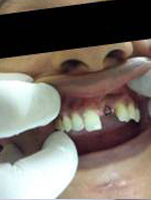

Pre Operation

Use of Bone Graft & GTR membrane for an Implant

Bone Graft in Extraction Socket